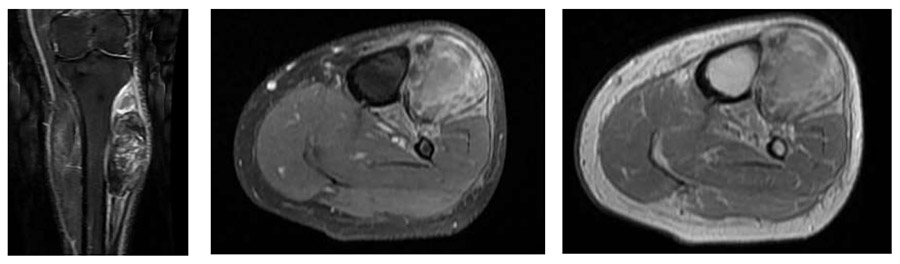

Ameliyat Öncesi: MR’da tibia korteksi üzerine oturmuş düzensiz sınırlı heterojen kitle etrafında ödem görülmekte